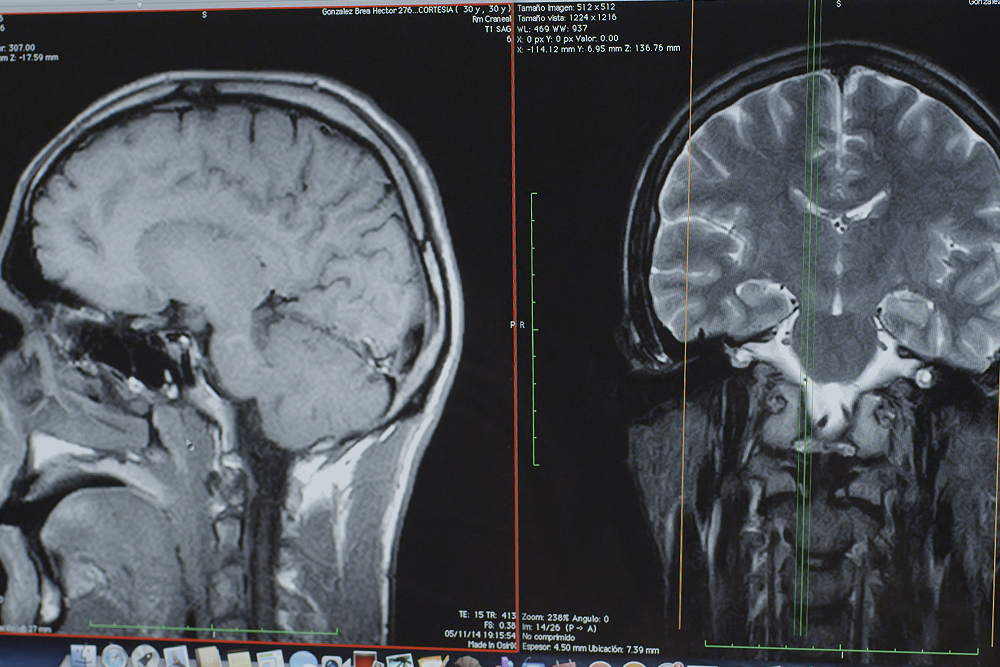

RESONANCIA MAGNÉTICA ABIERTA DE ALTA RESOLUCIÓN

Resonancia Magnética abierta de Alta resolución: 2048 x 2048 pixeles - 256 cortes – 1mm de espesor potencial

"La imagen nítida de la salud"

Disponemos de una amplia capacidad de estudio al servicio de pacientes y profesionales médicos que lo requieran. Llevamos el diagnóstico a un nivel superior utilizando una tecnología más amable para el usuario, al disponer de una configuración abierta de alto rendimiento para estudios más detallados, más exactos, más minuciosos y de las máximas garantías, para llegar al detalle que se precisa sin escatimar esfuerzos y a cualquier parte del cuerpo que sea necesaria.

Gracias a esta avanzada tecnología de campo magnético permanente, les proporcionamos estudios diagnósticos a 2048 x 2048 píxeles de resolución de imagen, con un alcance potencial de 256 cortes a 1 mm de espesor mínimo. La función de separación de grasa y agua se realiza directamente durante el estudio, al igual que en las resonancias más avanzadas, y el sistema RADAR que posee, corrige los movimientos involuntarios del paciente evitando así errores durante la realización de la prueba. Analizamos el eco de retorno con un avanzado software permitiendo imágenes más nítidas, más estables y de mayor contraste, como la tecnología de predicción y supresión de las corrientes de remolino (ECC system) incorporadas en el propio imán. Con todo ello el potencial de diagnóstico aumenta exponencialmente, permitiéndonos localizar y analizar los artefactos más pequeños que determinada patología pueda originar. Leer más...